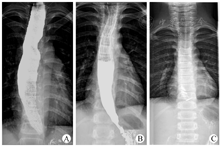

所有患儿术后随访3~17个月,所有患儿吞咽困难等症状较术前均明显缓解,术后Eckardt评分均小于3分,15例患儿POEM治疗效果良好。典型病例TBE检查结果见图2。术后3个月Eckardt评分及TBE 5 min钡剂高度较术前明显降低,差异有统计学意义(均P<0.001,表1)。术后3个月身体质量指数较术前明显增加,差异有统计学意义(P=0.009)。

儿童AC的术后疗效评估具有一定的特殊性。POEM术后常使用Eckardt评分、食管测压、食管钡餐造影、生活质量评分等作为评估手段,其中Eckardt评分为患儿主观症状评估,因儿童难以准确表达主观感受,可能存在一定程度的测量偏倚,需结合客观数据整体评估疗效。食管高分辨率测压可提供精确、客观的食管动力学数据,评估手术疗效准确度高,但检查过程较为痛苦,术后随访儿童常难以接受[18,19]。TBE由传统钡餐造影中发展而来,可观察食管直径及食管排空情况,有研究建议将TBE作为评估AC术后疗效的主要方式[20]。本组选择Eckardt评分、TBE 5 min钡剂高度及身体质量指数评估手术疗效,三者均提示术后较术前有明显改善,差异有统计学意义,POEM术治疗儿童AC有良好的手术效果。